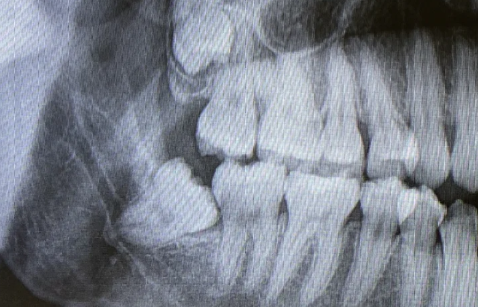

经过多年的临床经验观察有些人拔掉智齿确实会出现面部凹陷的情况,类似于牙套脸!网络上许多说拔完智齿带牙套许多形成牙套脸没恢复的其实就是因为拔智齿的原因,因为智齿拔掉以后有些人会出现末端牙槽骨凸吸收会形成不可逆的面容苍老。